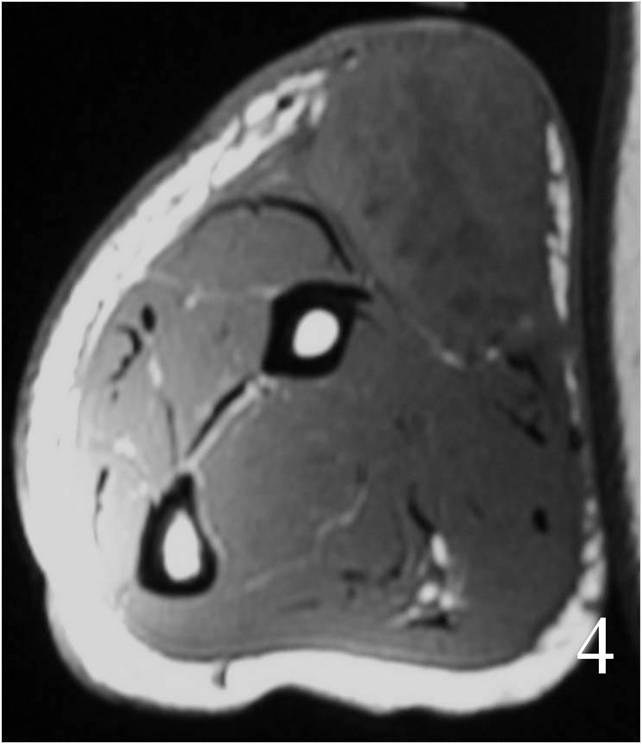

Large heterogeneous mass (Fig. 4, 5, 6)

Fig. 4 MRI of a leiomyosarcoma of the forearm shows a mass isointense to muscle on T1W image, heterogeneous on T2W (Fig. 5) and enhances with contrast T1W fat suppressed (Fig. 6)